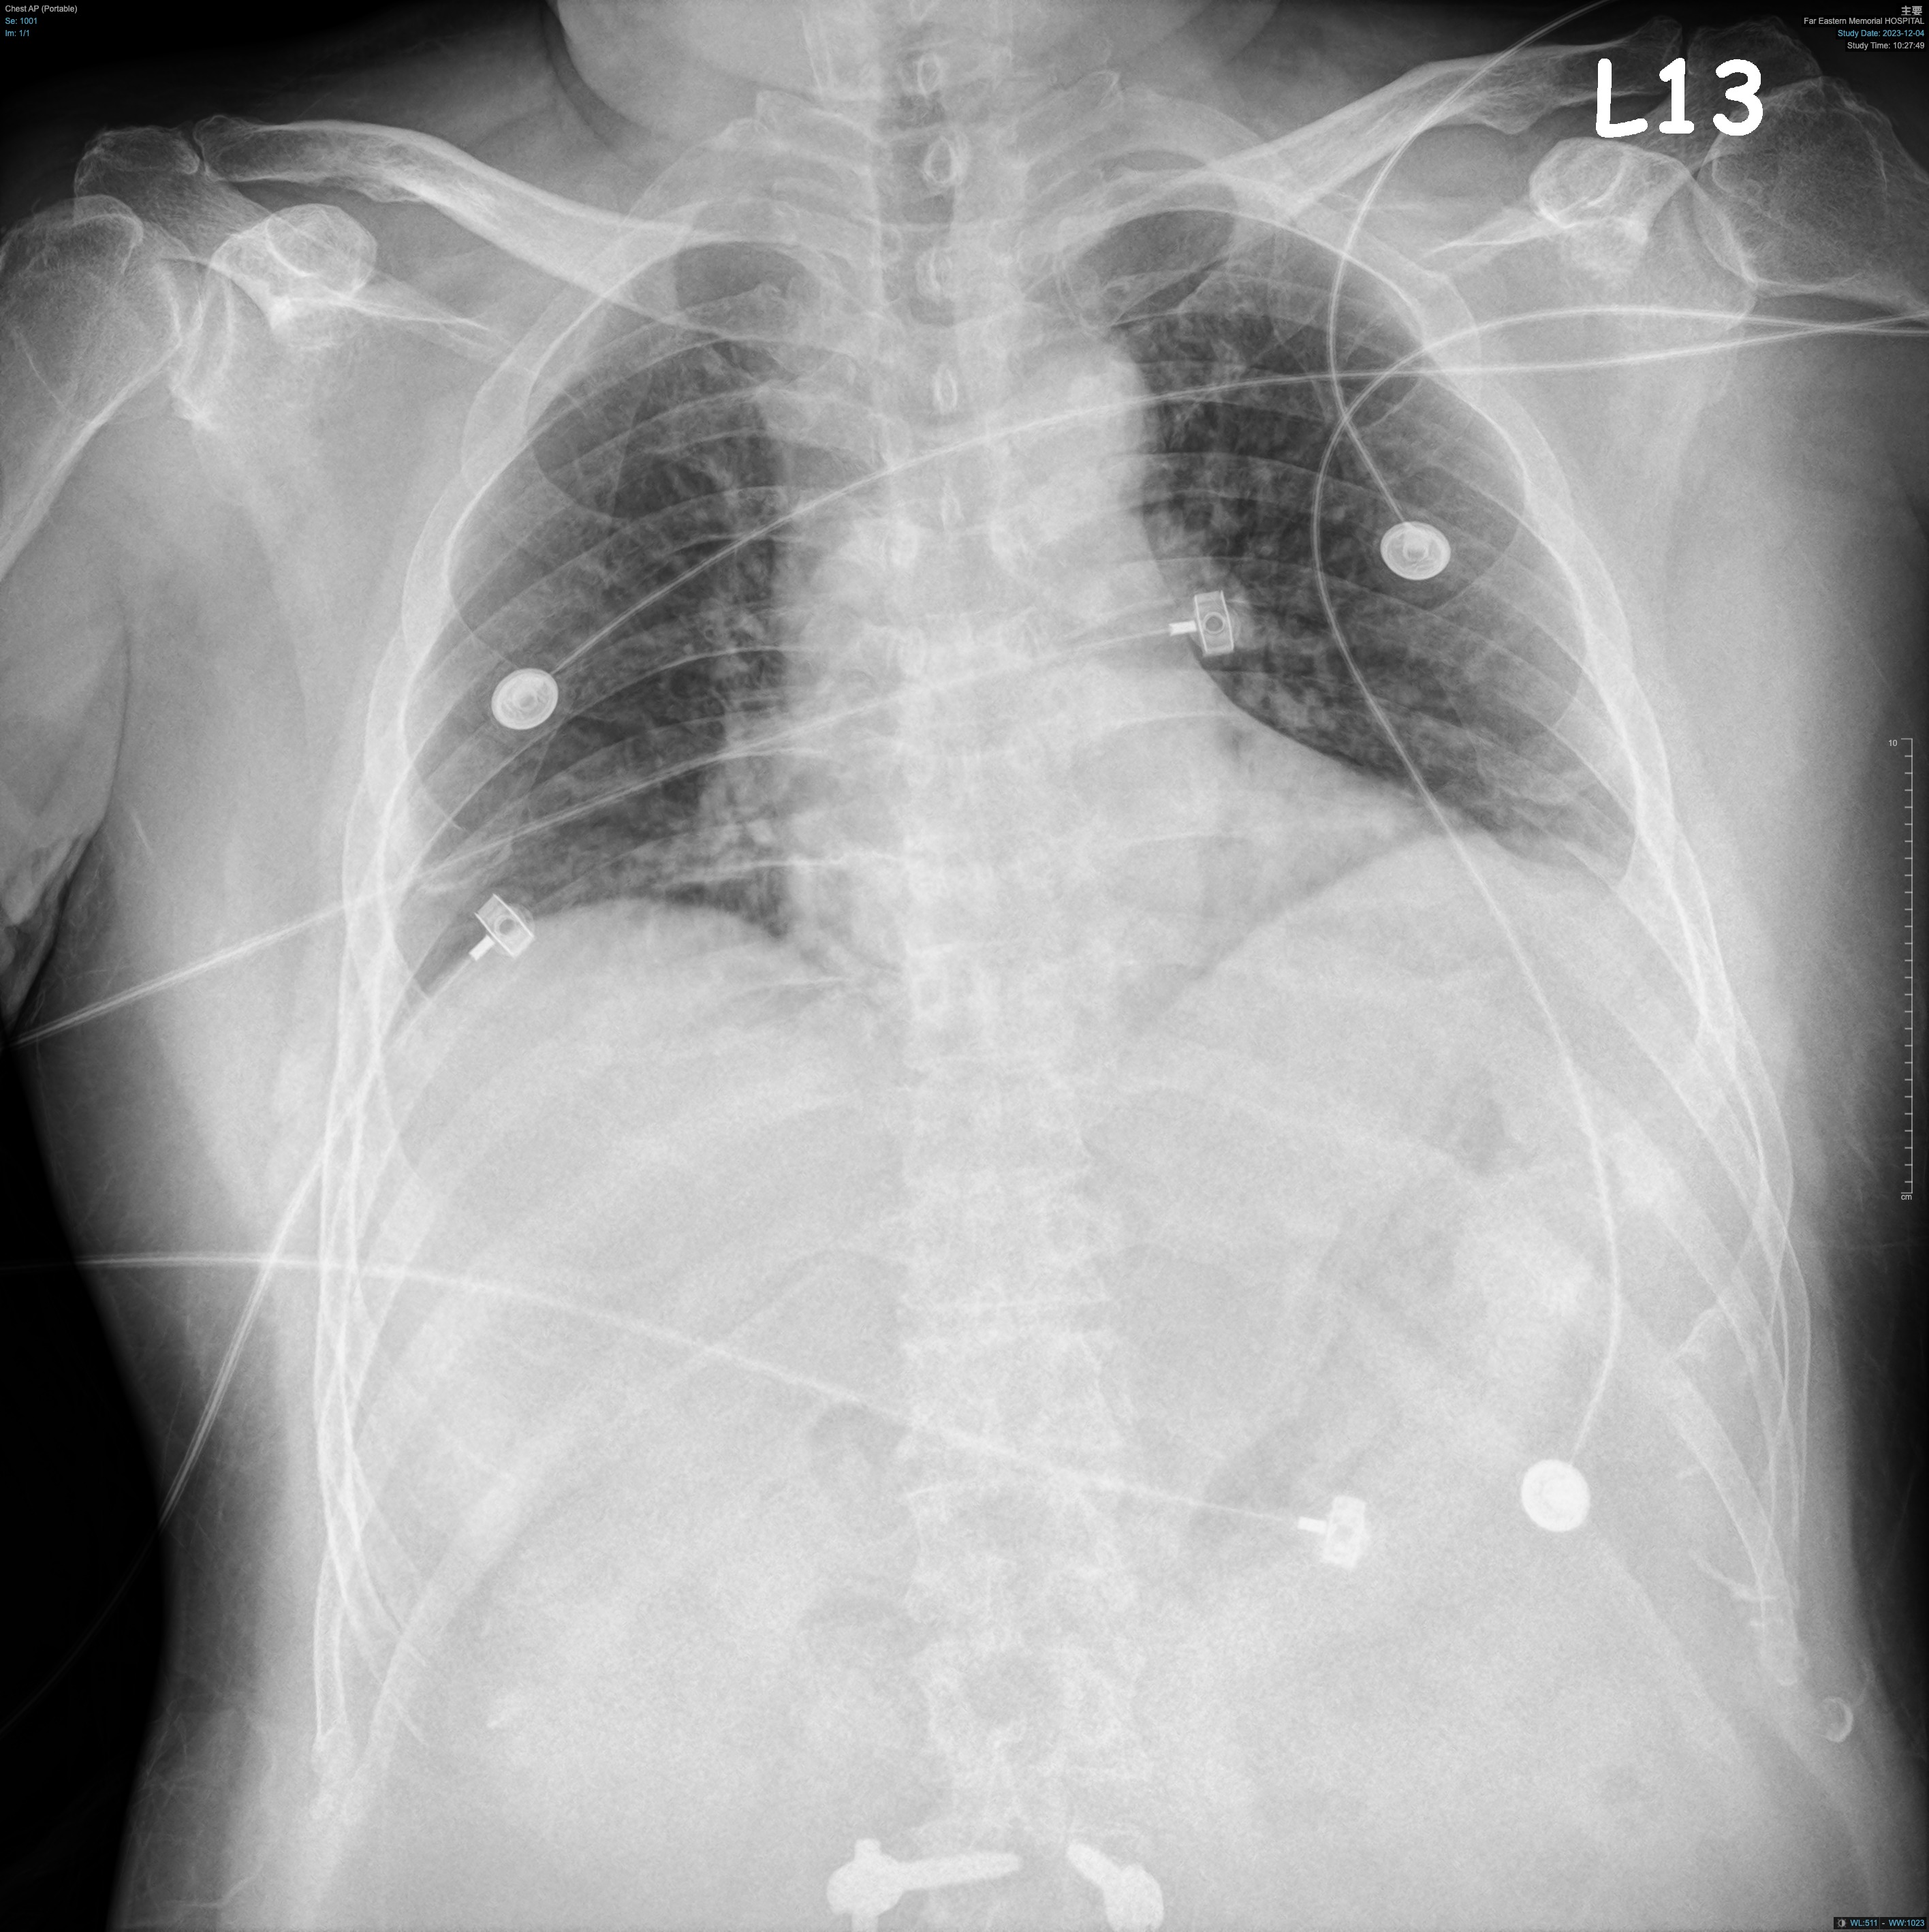

This 63-year-old male had coronary artery disease, status post angioplasty and stenting to the left anterior descending and right coronary artery (RCA). He presented to the ER with chest pain since the previous night. Examination showed stable vitals. ECG revealed sinus rhythm and Q-S pattern in leads II, III, and aVF. Elevated cardiac enzymes and echocardiography with fair ejection fraction without RWMA confirmed NSTEMI. He was admitted to the ICU, and coronary angiography planned.